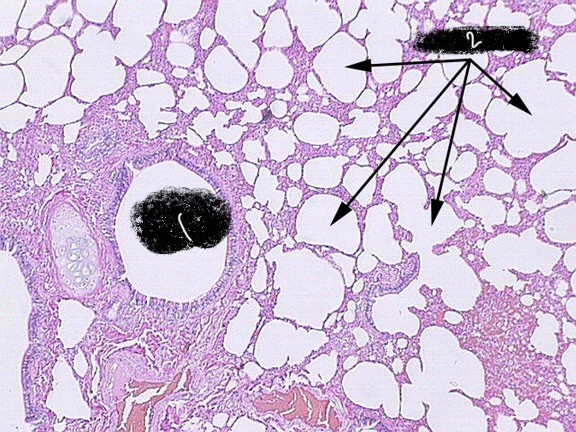

2

alveoli

bronchiole